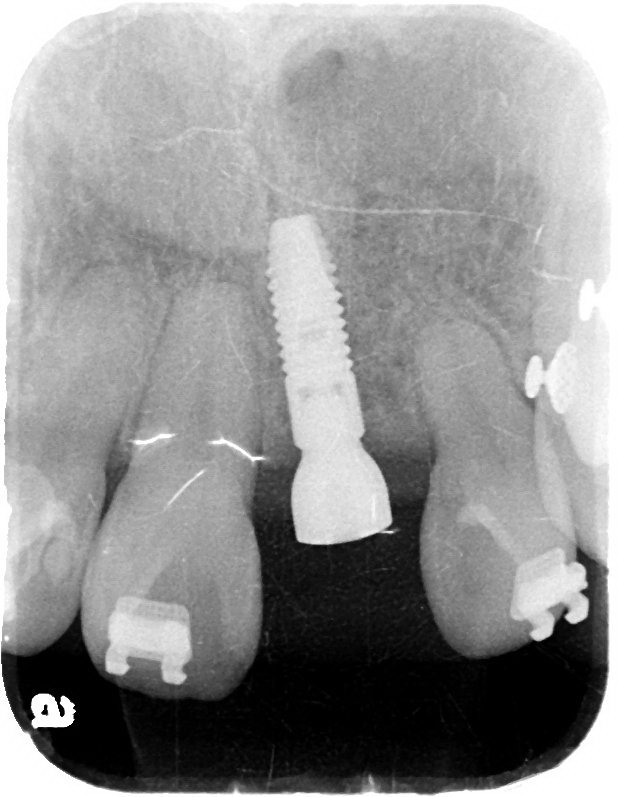

Post dental implantation.

Bone resorption after extraction